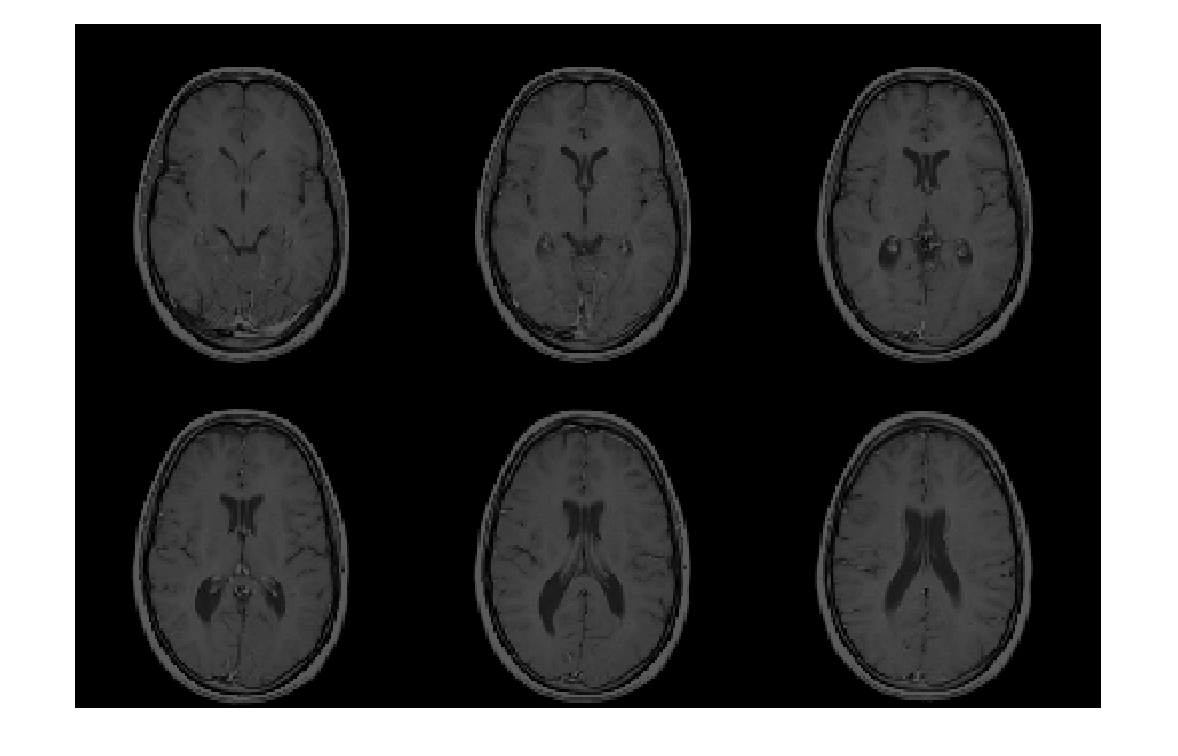

Считайте данные изображения из файла Analyze 7.5.

X = analyze75read('brainMRI');

Просмотрите данные. Во-первых, потому что формат Analyze 7.5 использует радиологическую ориентацию (LAS), инвертируйте данные для отображения правильного образа в MATLAB.

X = flip(X);

Затем измените данные, чтобы создать массив, который может быть отображен с помощью montage. Выберите системы координат 12 - 17.

Y = reshape(X(:,:,12:17),[size(X,1) size(X,2) 1 6]);

montage(Y);

Figure contains an axes object. The axes object contains an object of type image.